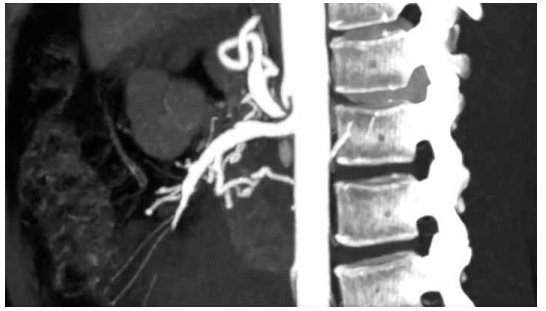

Foi realizada uma angiotomografia de abdome, cuja imagem é apresentada a seguir:

(Arquivo pessoal; imagem usada com autorização)